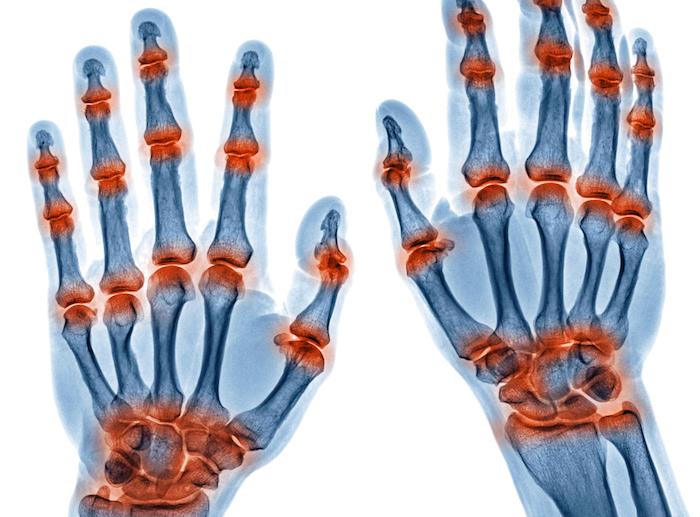

Dans une étude contrôlée versus placebo, une seule perfusion de 1 000 mg d’un anticorps anti-CD20 (rituximab), dirigé contre les cellules immunitaires à l’origine de la production des anticorps (les lymphocytes B), retarde de 12 mois les premiers signes cliniques de la polyarthrite rhumatoïde, et donc la maladie elle-même.

En plus de donner une piste de traitement préventif pour la maladie rhumatoïde, cette étude bien menée apporte des preuves en faveur du rôle majeur des lymphocytes B dans le déclenchement de la polyarthrite rhumatoïde (rôle pathogénique).